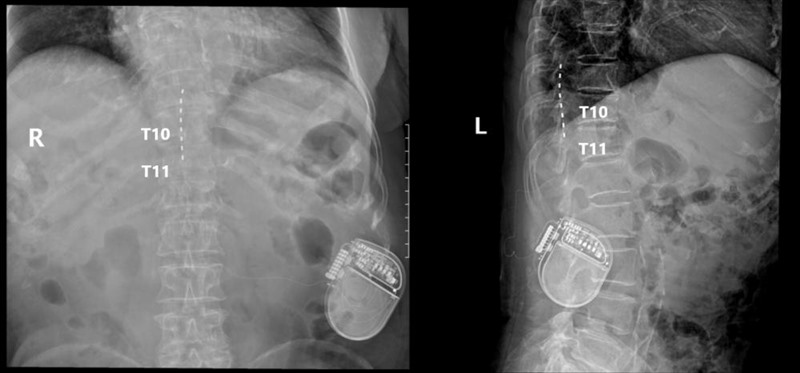

手术台上测试,开启刺激器后,周婆婆能清晰感觉到双腿有微弱电流酥麻感,双腿疼痛感觉立即减弱,测试效果显著。回病房当晚,双下肢的疼痛完全消失,第二天查房时周婆婆激动地表示,“折磨了我这么久的疼痛神奇地消失了,终于不痛了,腿脚也热乎了!”她的脸上露出了久违的笑容。术后三天,周婆婆几乎都在补觉,由于睡得好,精神状态也好了很多。楚磊表示,“后期,在长期电刺激及成熟的糖尿病足护理下,患者下肢血管问题会逐渐恢复,下肢远端缺血将得到改善。”

▲术后复查可见电极放置在T9-T11节段脊髓后方/图源 重医附二院疼痛科